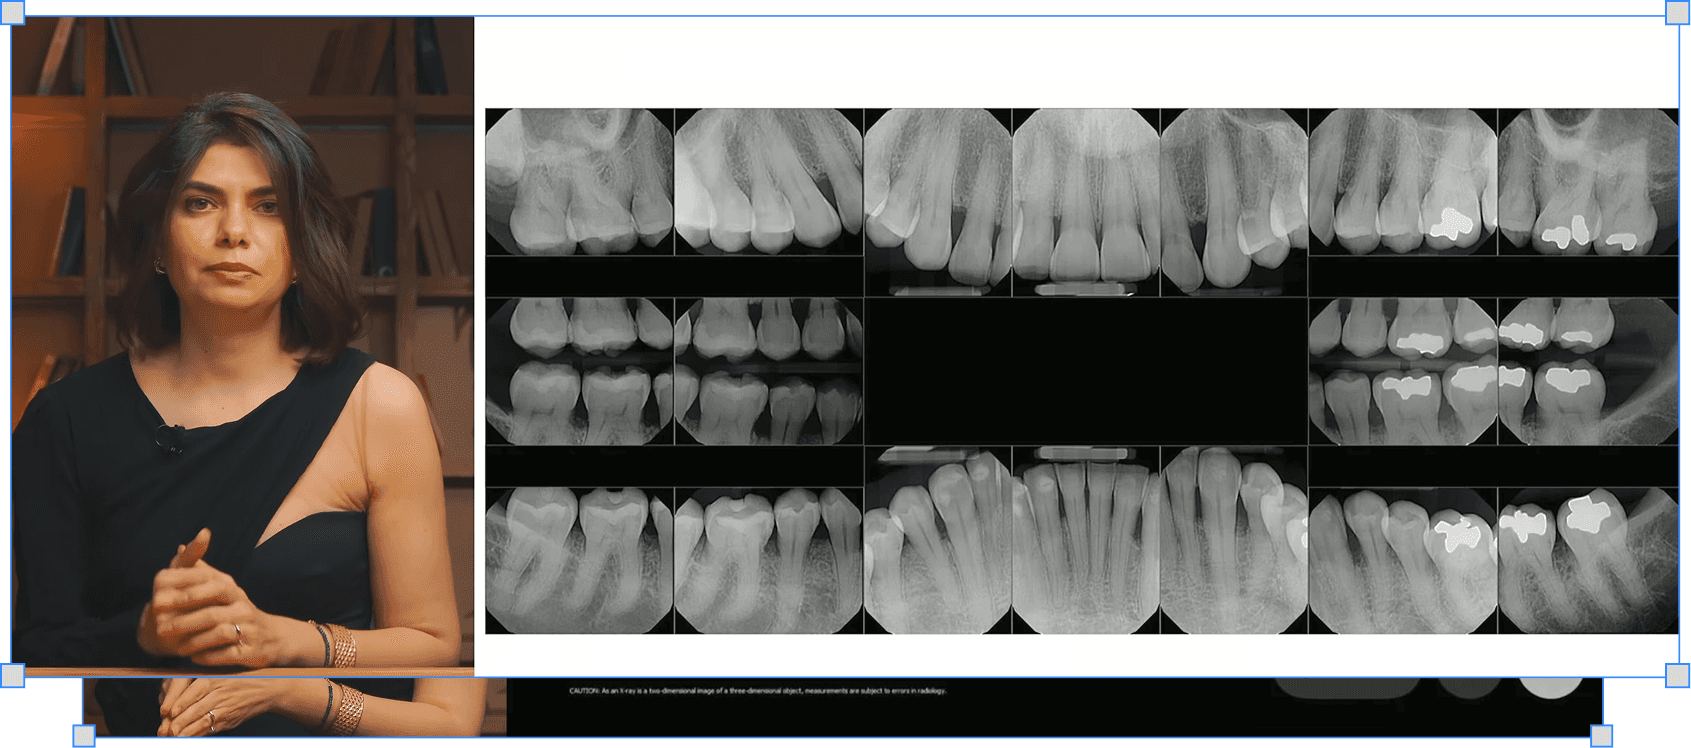

Ельміра Алішова

Діагностика пародонтиту: PSR-тест, зондування і серія прицільних знімків

PSR-тест, зондування без болю і прицільна серія — повна діагностична картина за класифікацією